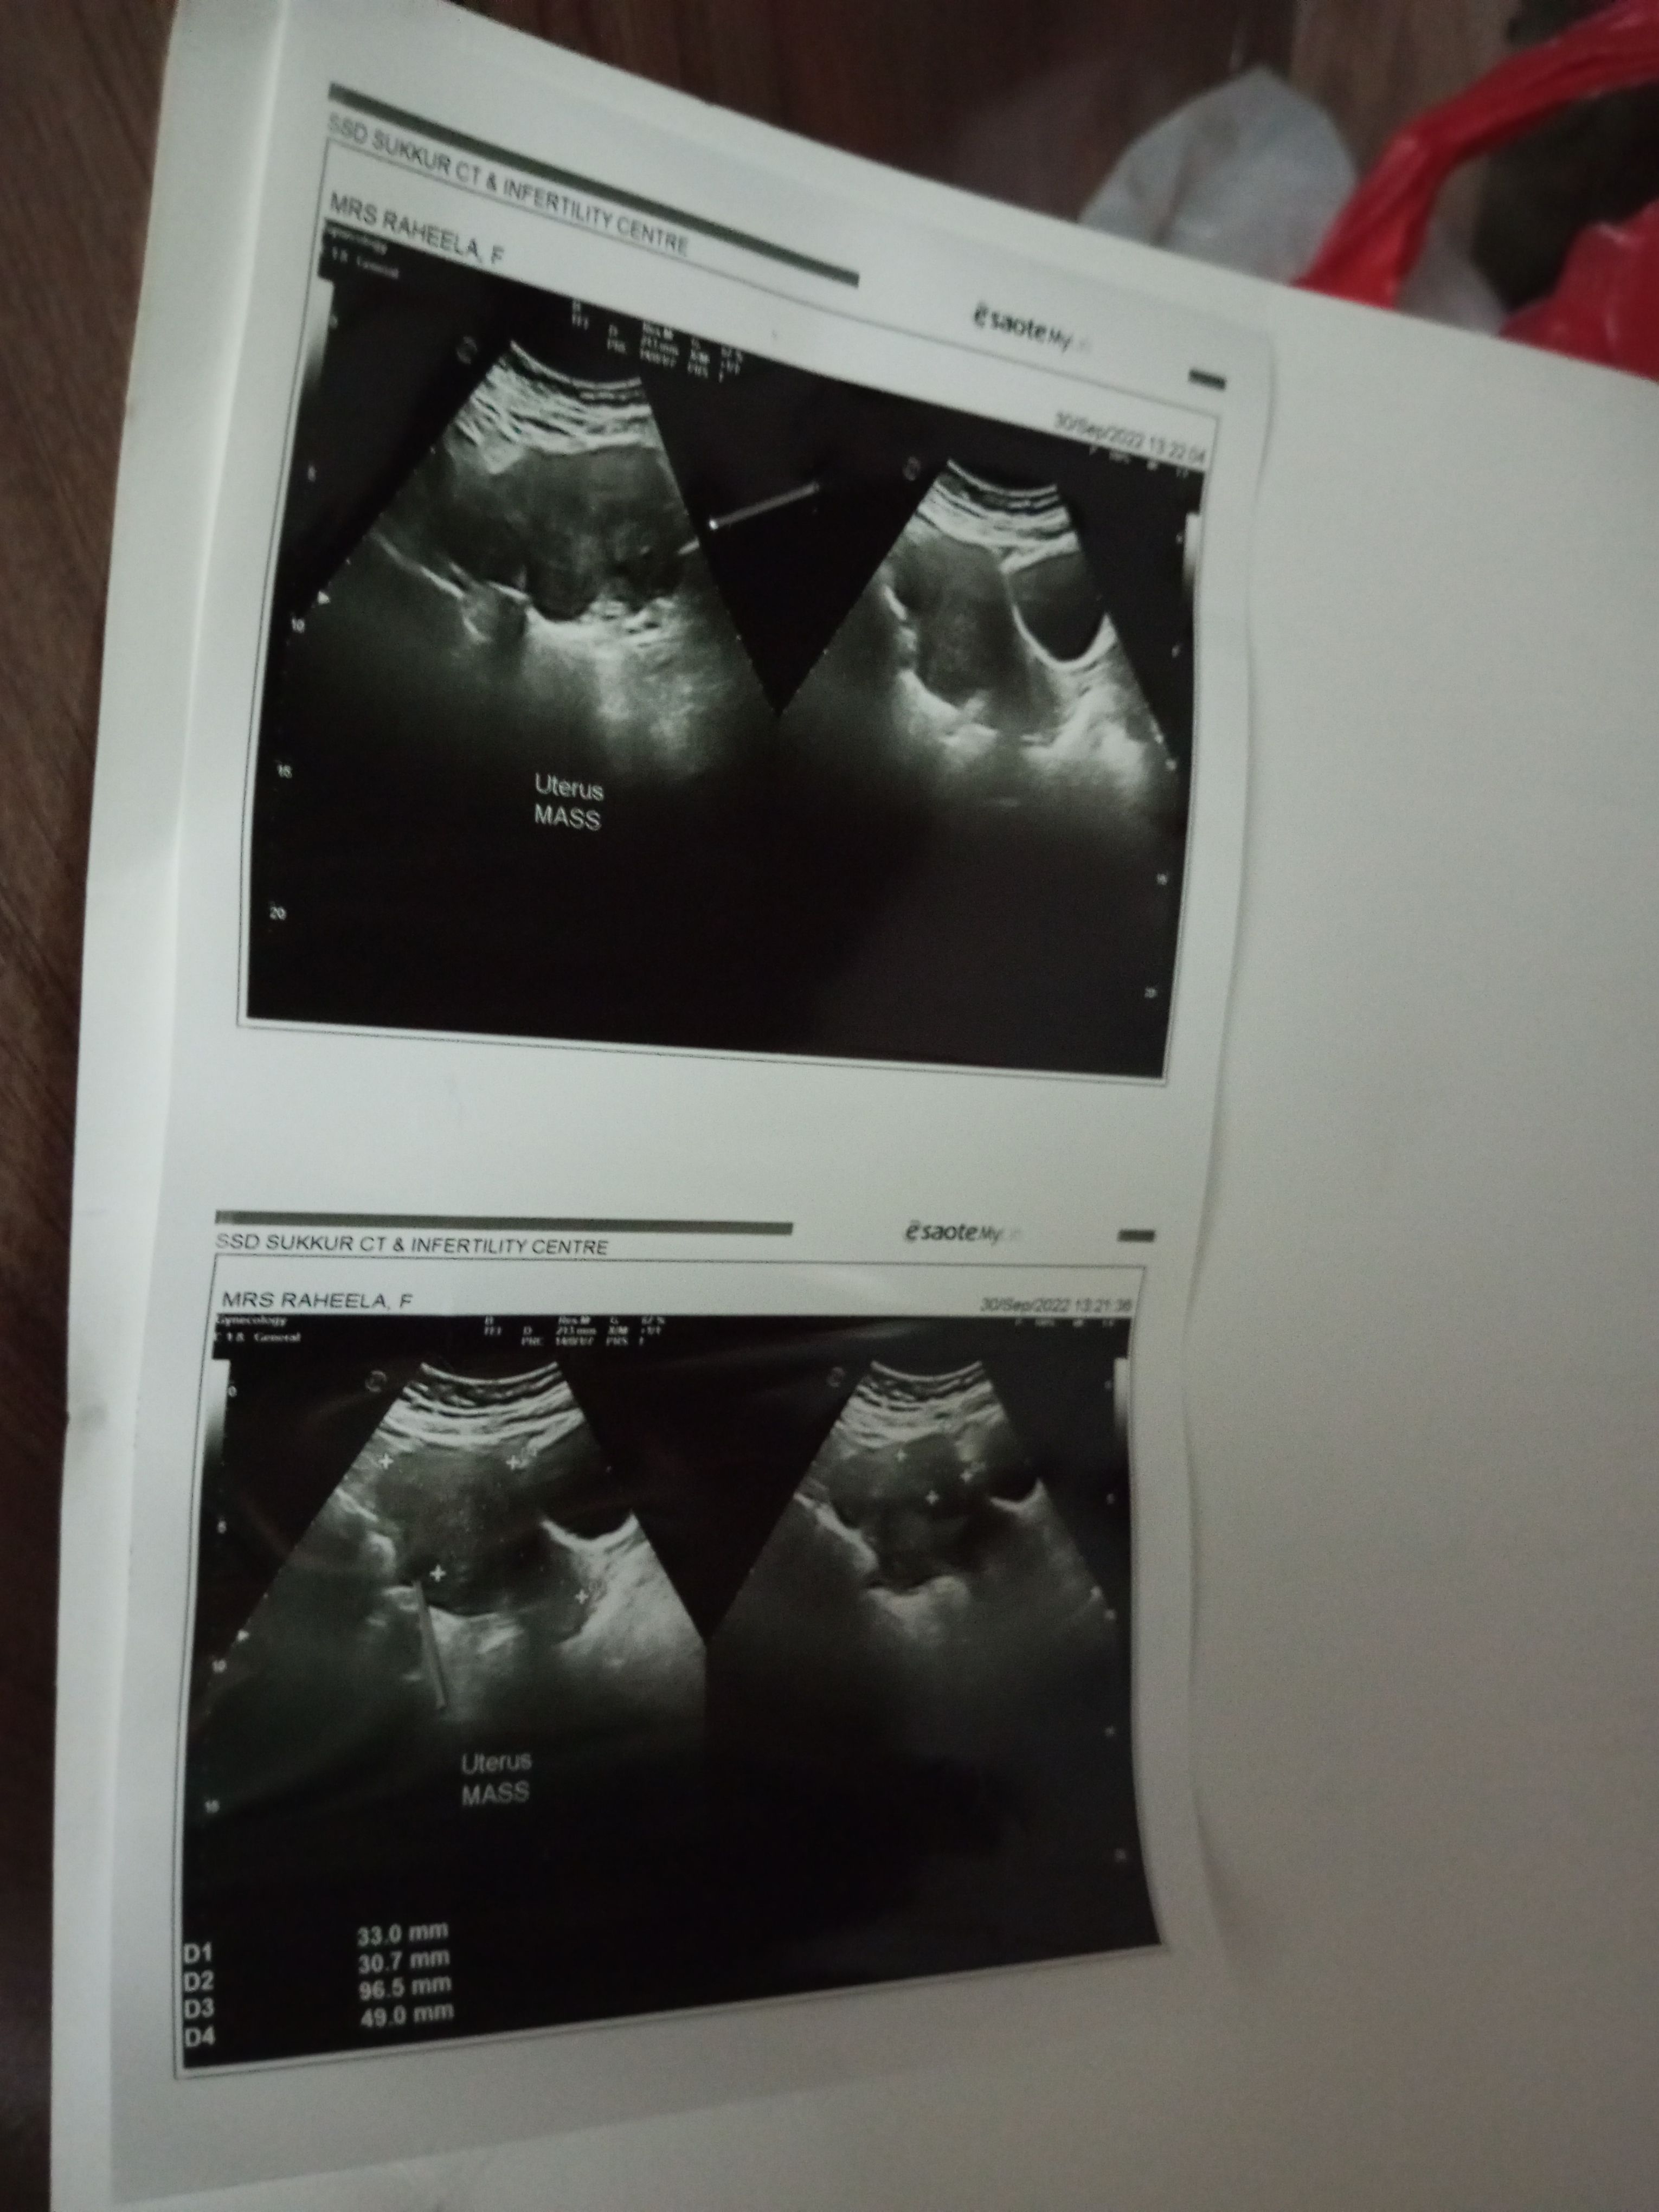

Asking For Self, Female 38, shikarpur

pregnancy ho jai ge plz bata dain